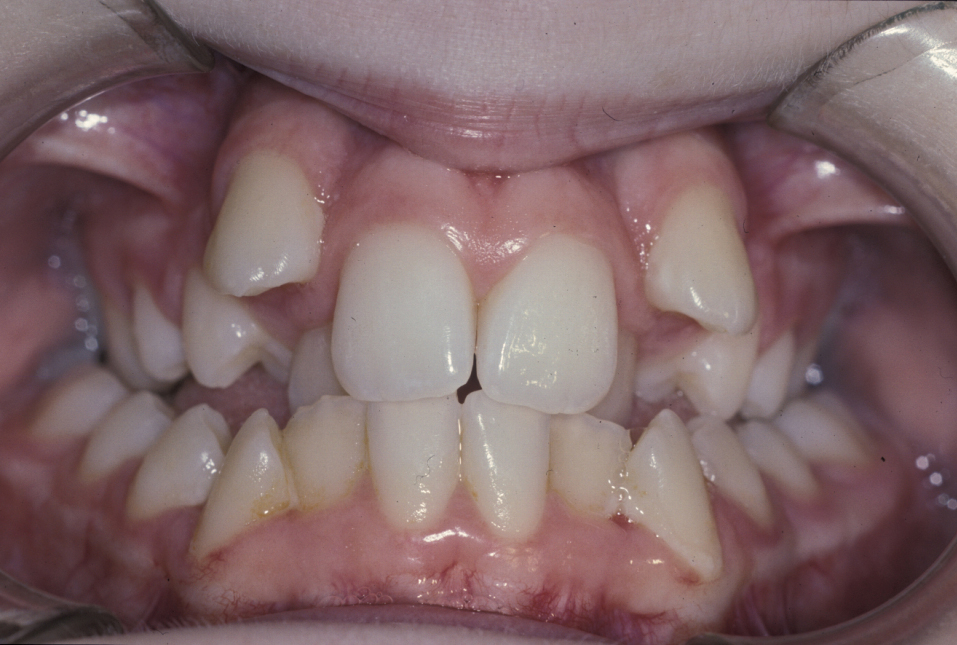

The molar and incisal relationships are examined visually and are formally documented by photographs (see Figure 5, Figure 6 and Figure 7 for examples) and study models (see below).

Figure 5: Intraoral view showing a class III malocclusion (underbite).

Figure 6: Intraoral view showing a class III malocclusion (underbite).

Figure 7: Intraoral view of a class III malocclusion (underbite).